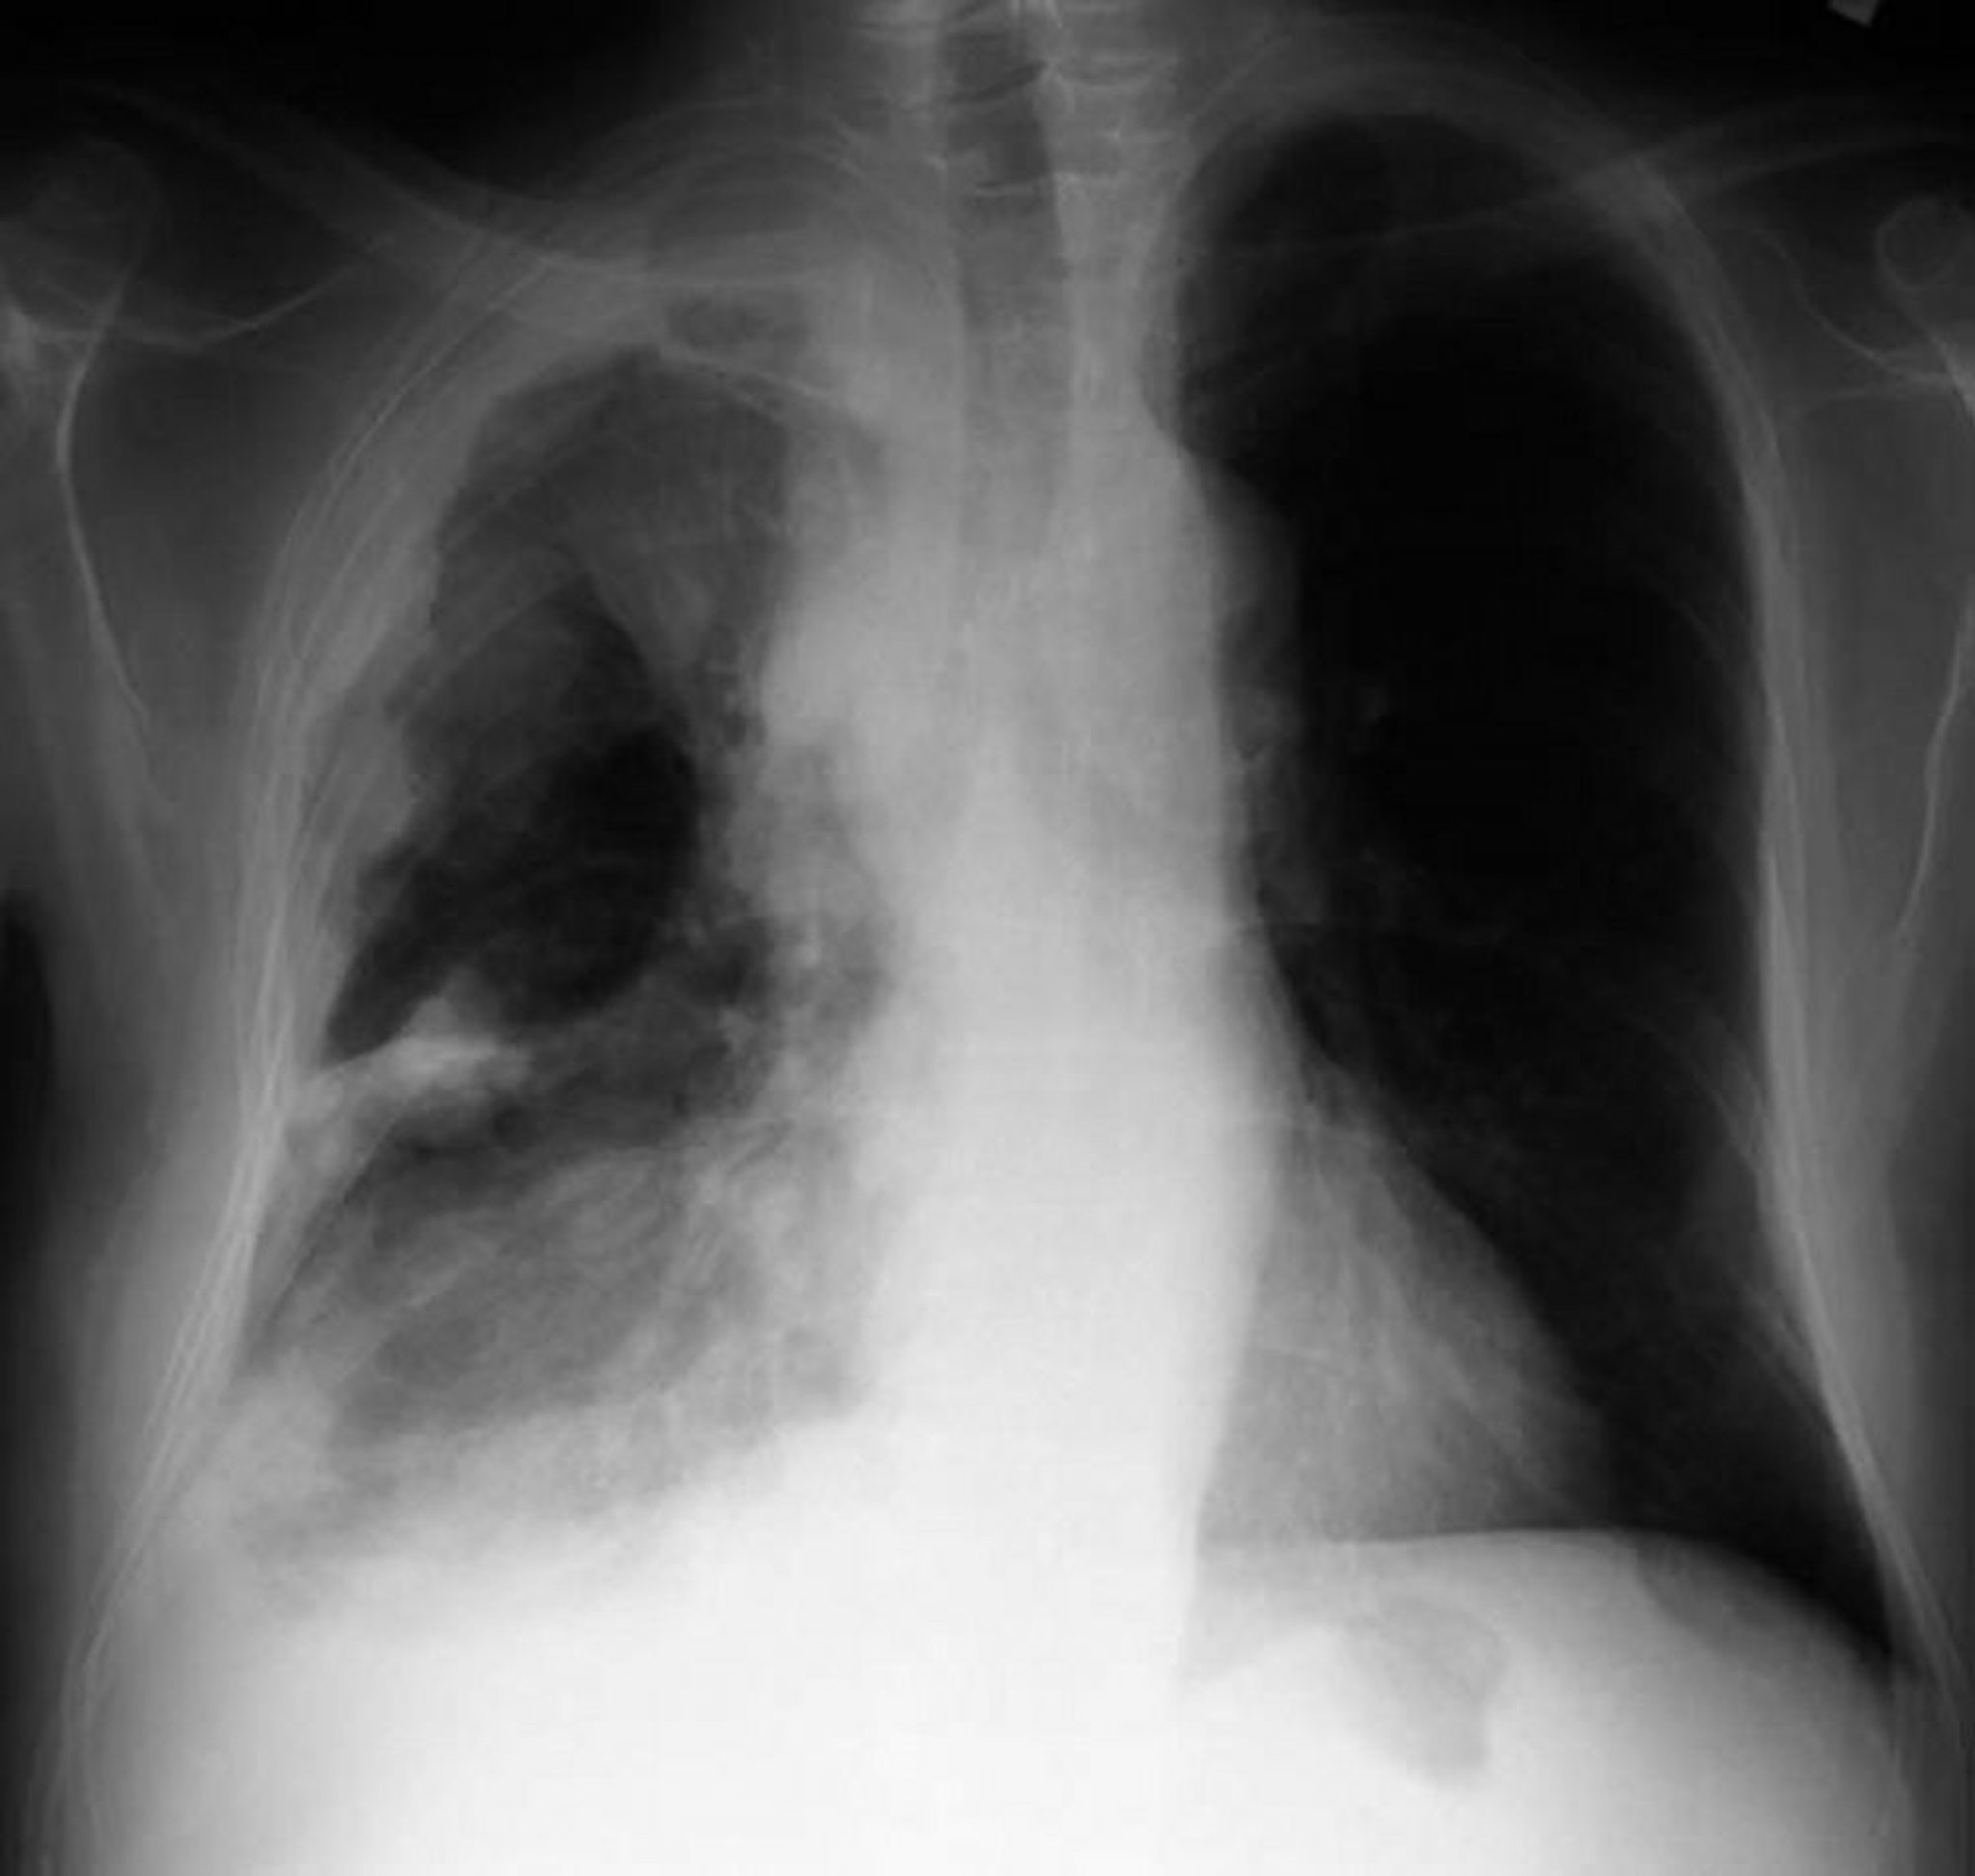

X-quang ngực ở một bệnh nhân ung thư trung biểu mô màng phổi cho thấy dày màng phổi với các khối nốt sần trên màng phổi.

Được sự cho phép của nhà xuất bản. Theo Huggins J, Sahn S. Trong Bone's Atlas of Pulmonary and Critical Care Medicine. Biên tập bởi J Crapo. Philadelphia, Current Medicine, 2005.